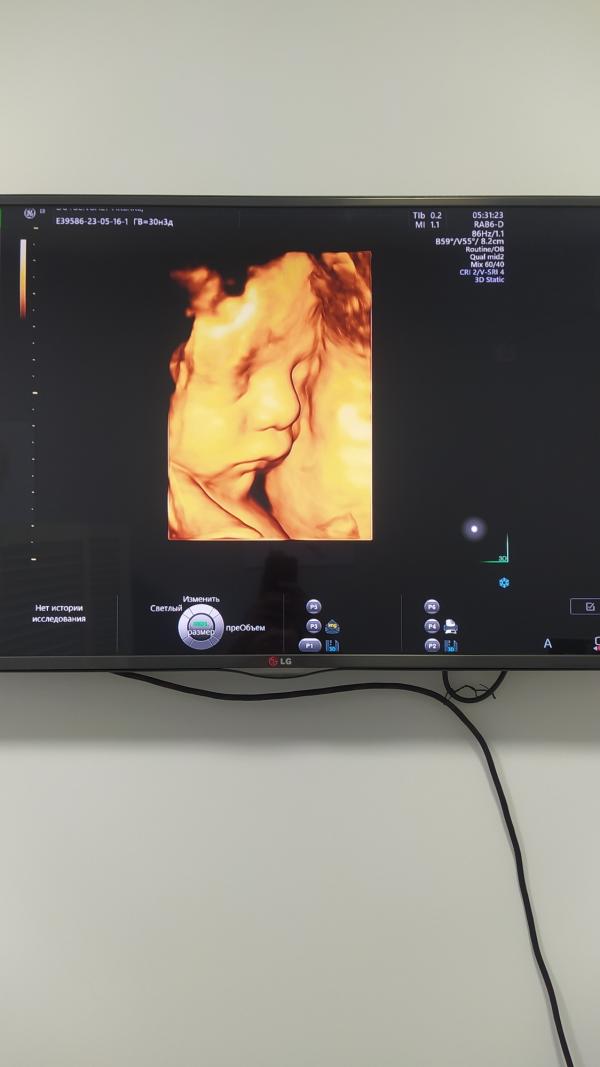

Сегодня прошла 3 скрининг 😍 На сына похож что ли малыш♥️

Так четко показали лицо,у кого скрининг проходили?

Дармеде по Навои Калиакпарова Индира. 👍🏻 Мне очень понравилась, всё от и до показывает и объясняет.